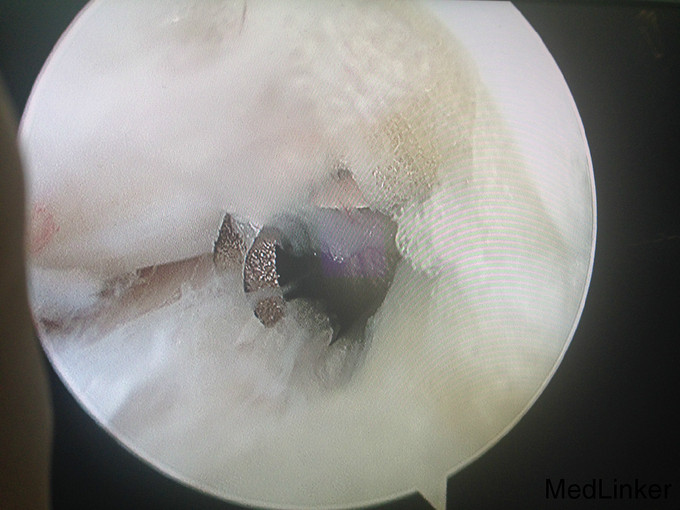

左踝扭伤后肿胀疼痛伴活动受限半年

查体:左腓肠肌萎缩,左踝轻度肿胀。左踝关节ROM较对侧降低,以背伸活动受限最明显。距腓前韧带处未及明显压痛。左踝内、外侧关节间隙压痛(+)。ADT(-),外侧应力试验(-)。左下肢肌张力正常、感觉正常。 辅检:MRI示“左踝关节积液”

诊断:左踝关节创伤性滑膜炎 治疗:左踝关节镜下滑膜清理、胫骨前缘成形

随访:患者术后即刻踝关节活动度恢复正常,2周恢复正常行走。 讨论:踝关节扭伤很常见,扭伤后会发生各种各样的情况。此患者扭伤后继发了滑膜炎,并伤及了关节软骨。这种情况应进行关节镜手术治疗。此外,核磁共振对关节疾患的诊断也是有限的,关节镜才是黄金标准。